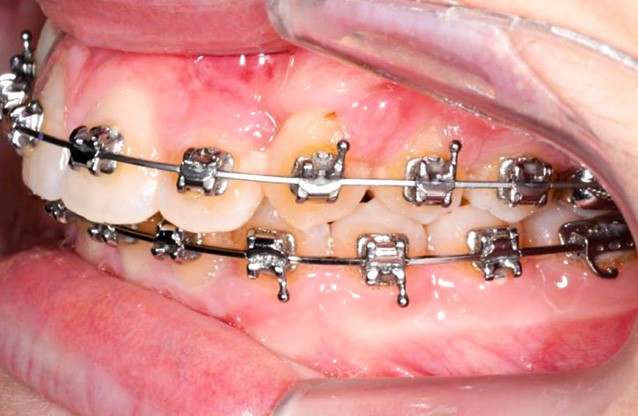

Les maillons de la chaînette du dispositif de traction sont sectionnés progressivement de manière bilatérale à chaque rendez-vous à mesure que les canines sont déplacées en direction vestibulaire et le bras TMA est systématiquement religaturé au premier maillon transmuqueux avec une ligature métallique .010. L’ensemble est sécurisé par une goutte de composite fluide photopolymérisé.

Une fois que la partie en alliage à mémoire de forme de l’arc transpalatin a retrouvé sa forme initiale, l’arc est désinséré. Les U latéraux et les lames d’insertions en acier sont réglés dans les trois sens de l’espace à l’aide d’une pince 139 pour corriger l’inclinaison mésio-distale, le torque et augmenter la dérotation de 16 et 26 pour assurer une traction supplémentaire des canines incluses en direction vestibulaire. Les bras d’expansion des secteurs latéraux de l’arc transpalatin sont également sectionnés. Les bras vestibulaires en TMA sont activés dans le sens vertical pour une traction des canines vers le plan occlusal.

Un appareil multi-attache est mis en place avec une prescription MBT en .022 x .028. une fois les faces vestibulaires des canines maxillaires apparentes. 13 et 23 ne sont pas prises en charge dans l’arc pour éviter les effets parasites sur les dents adjacentes. Leur traction est poursuivie avec des élastiques de Classe II (1/4” – 3.5 oz) en port nocturne. Ces élastiques sont portés sur un bouton palatin pour la 23 afin de corriger sa rotation mésio-vestibulaire. Une fois les canines suffisamment proches du plan occlusal, elles sont prises en charge dans un arc continu en suivant les séquences suivantes : .014, .018 et .019 x .025 Niti. Une fois l’arc .019 x .025 en Niti en place pendant huit semaines, l’arc transpalatin est déposé. L’arcade mandibulaire suit cette même séquence d’arcs avec l’ajout d’un arc en acier .019 x .025 avec courbe de Spee inversée pour aider à la correction de la supraclusion.